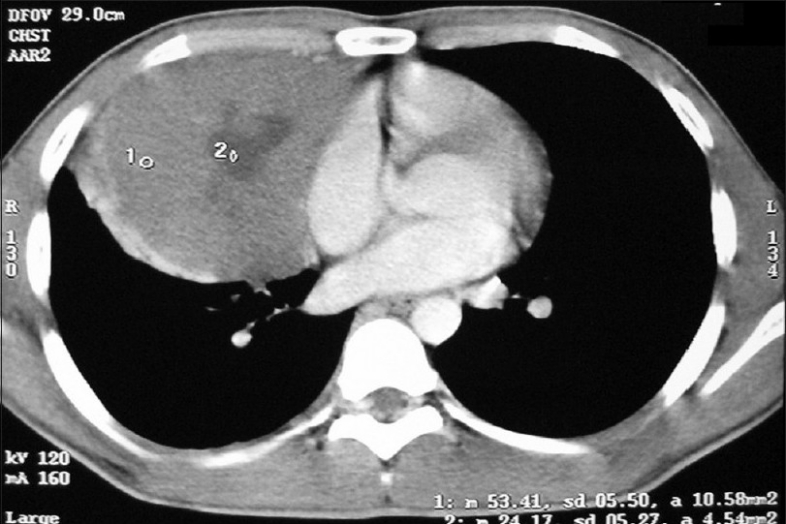

He presented in June 2007 with dull-aching retrosternal and right-sided chest pain with exertional dyspnea and dysphagia for solids. On examination, there was impaired note to percussion over the right mammary and infra-axillary regions with diminished breath sounds. A 3 ×3 cm mass was palpable over the epigastric region. Both testes were normal. Chest X-ray showed superior mediastinal widening with homogenous opacity in the right mid and lower zone [Figure 6]. CECT chest showed an anterior mediastinal mass extending into middle mediastinum with subpleural metastases to posterior segment of right lower lobe [Figure 7].

| Figure 7 CT chest (2007 ) shows recurrence of anterior mediastinal mass extenting into right side of chest